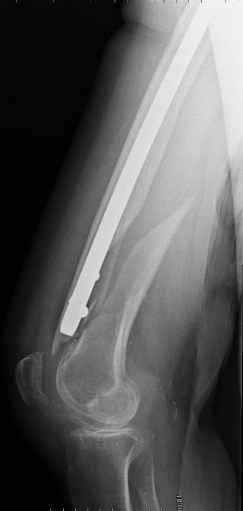

I should like know what is your preferred treatment for this fracture at

the tip of a long Gamma nail (on a healed subtrocantheric fracture : see

img).

The patient is a 81 years old lady with osteoporosis and important knee

arthrosis (as you can see).